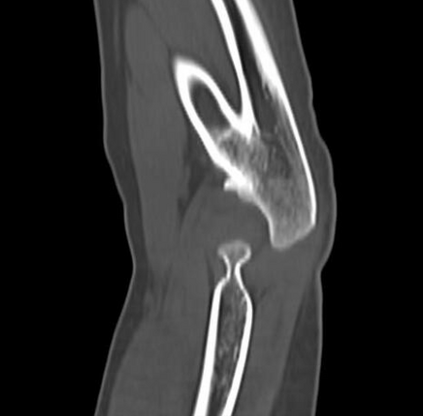

In this study, we aim to initiate the development of Radiology Foundation Model, termed as RadFM.We consider the construction of foundational models from the perspectives of data, model design, and evaluation thoroughly. Our contribution can be concluded as follows: (i), we construct a large-scale Medical Multi-modal Dataset, MedMD, consisting of 16M 2D and 3D medical scans. To the best of our knowledge, this is the first multi-modal dataset containing 3D medical scans. (ii), We propose an architecture that enables visually conditioned generative pre-training, allowing for the integration of text input interleaved with 2D or 3D medical scans to generate response for diverse radiologic tasks. The model was initially pre-trained on MedMD and subsequently domain-specific fine-tuned on RadMD, a radiologic cleaned version of MedMD, containing 3M radiologic visual-language pairs. (iii), we propose a new evaluation benchmark that comprises five tasks, aiming to comprehensively assess the capability of foundation models in handling practical clinical problems. Our experimental results confirm that RadFM significantly outperforms existing multi-modal foundation models. The codes, data, and model checkpoint will all be made publicly available to promote further research and development in the field.